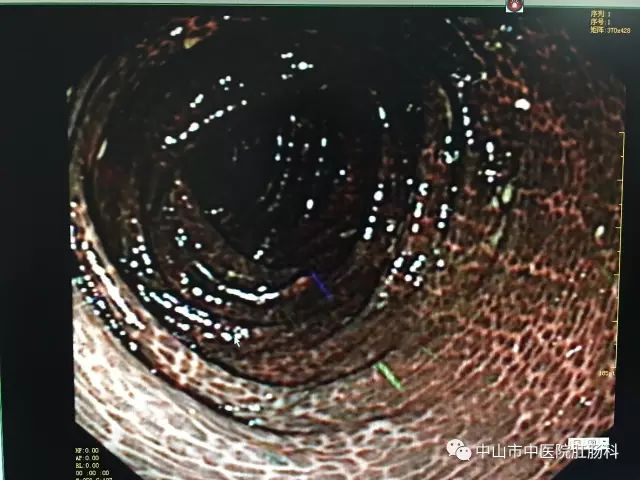

医生说,这样的肠粘膜改变,称之为“大肠黑变病”,在日常检查过程中检出率不低,但是像这位患者这样黑的,实属罕见。而正常的肠子,是粉红粉红、血管纹理分明的,如下图:

大肠黑变病

镜下表现为结肠黏膜光滑、完整,可见浅棕色、棕褐色或黑色的色素沉着,呈条纹状、斑片状、虎皮状改变,可网络状间断或连续分布,肠腔明显变暗。